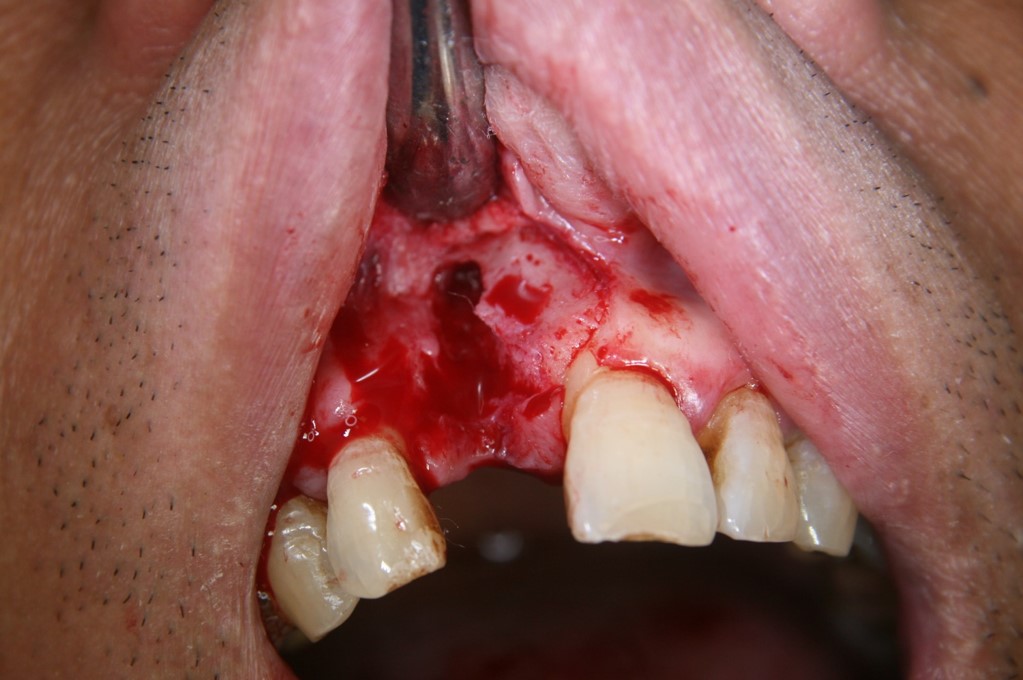

Fig 2. A PLGA alloplast bone grafting material was placed and molded to shape the area.

Figure 2

Fig 5. Patient presented with a periodontal defect.

Figure 5

Fig 6. A flap was required to expose and clean the defect area (ie, exposed root, furcation) using ethylenediaminetetraacetic acid (EDTA).

Figure 6

Fig 7. PLGA alloplast bone grafting material was placed and molded into shape and, once the bone material solidifies, a membrane would be placed and the area closed with the soft tissue.

Figure 7